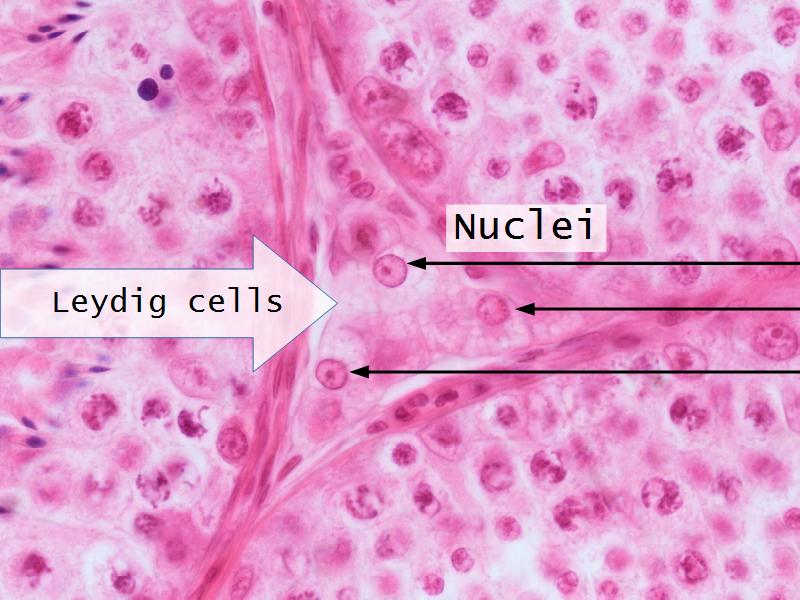

- D1: Leydig cells

- D1: Leydig cells = testosterone